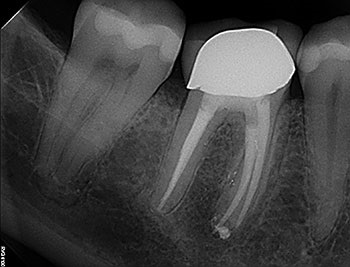

Case 6: A lateral canal

Furcal lesions are generally caused by furcation or lateral canals. However, sometimes furcation lesions can arise from VRF and result in extraction. These fractures can occur anywhere, but often follow the grooves in occlusal anatomy. So when a furcation radiolucency is seen, it is prudent to investigate its etiology and not just extract it under the assumption of a vertical root fracture.

Cases with lateral canals that extend from the pulpal floor into the furcation can be difficult to treat. Disinfection using sodium hypochlorite is critically important, as is a long soak. A calcium hydroxide intracanal medicament should be packed into the floor of the pulp chamber between appointments. Sometimes, it is possible to locate the lateral canals and negotiate them with small, curved stainless steel files. If a lateral canal is not disinfected, ongoing symptoms and eventually a furcal lesion of endodontic origin can be expected. After NSRCT has been completed, an adhesive liner or buildup can be placed on the pulpal floor to prevent bacterial reentry.

Endodontic Root Fracture Case Series

Fig. 23: Preop PA.

Fig. 24: Lateral canal.

Fig. 25: Postop PA.